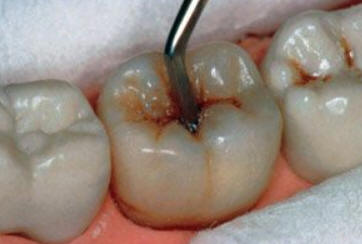

Sólo se lleva a cabo en  cavidades pequeñas ( que involucra solo la dentina ) y en aquéllas que son accesibles para los instrumentos de mano. Con el instrumental de mano se elimina la dentina desorganizada e infectada hasta llegar a la dentina desmineralizada. Ver figura inferior.

Se aísla el campo operatorio con rollos de algodón. Se limpia la cavidad con una torunda de algodón embebida en agua y luego se seca con torunda. Se utiliza la hachuela para ampliar la cavidad de caries, luego se elimina la caries con  cucharitas o excavadores.

Preparar el ionómero vítreo como indican la instrucciones del fabricante. Obturar con ionómero la cavidad y las fisuras remanentes.

Frote el  índice enguantado con vaselina y el material del relleno se aprieta firmemente con el dedo en el diente. Espere unos minutos y comience el tallado del material con el azadón.

La obturación terminada debe abarcar todas las fosas y fisuras,.